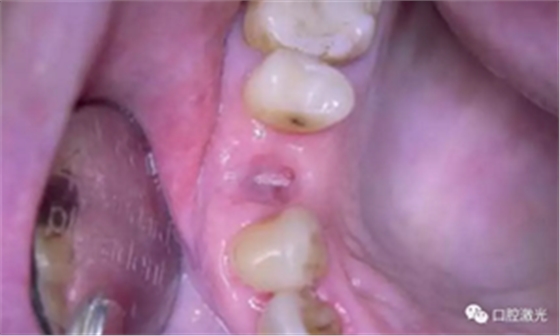

术后3天